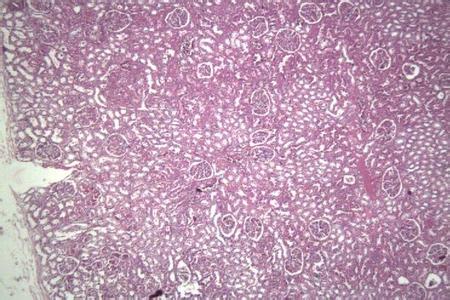

单纯性紫癜是很常见的良性出血性疾病,常自发性地出现皮肤,尤其是两下肢瘀斑,尽管其病程较长,且反复发作,但是此病不经治疗便可以自行消退,一般对健康无严重危害性,预后良好。

当发病时,单纯性紫癜的临床表现为反复发作的皮下瘀斑,常见于下肢、臀部,易发作于月经期,不予治疗瘀斑可以自行消退,一般无其他出血倾向,健康状况良好。